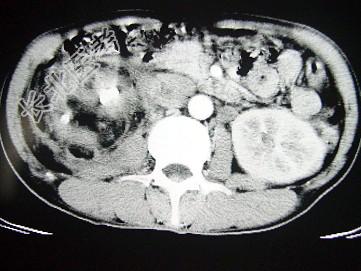

- 单项选择题女,43岁, 右腰部疼痛不适2年余,加重3天, CT及MRI检查如图,应诊断为 ( )

A、右肾癌

B、右肾错构瘤合并出血

C、右肾脂肪瘤

D、右肾脂肪肉瘤

E、右肾海绵状血管瘤